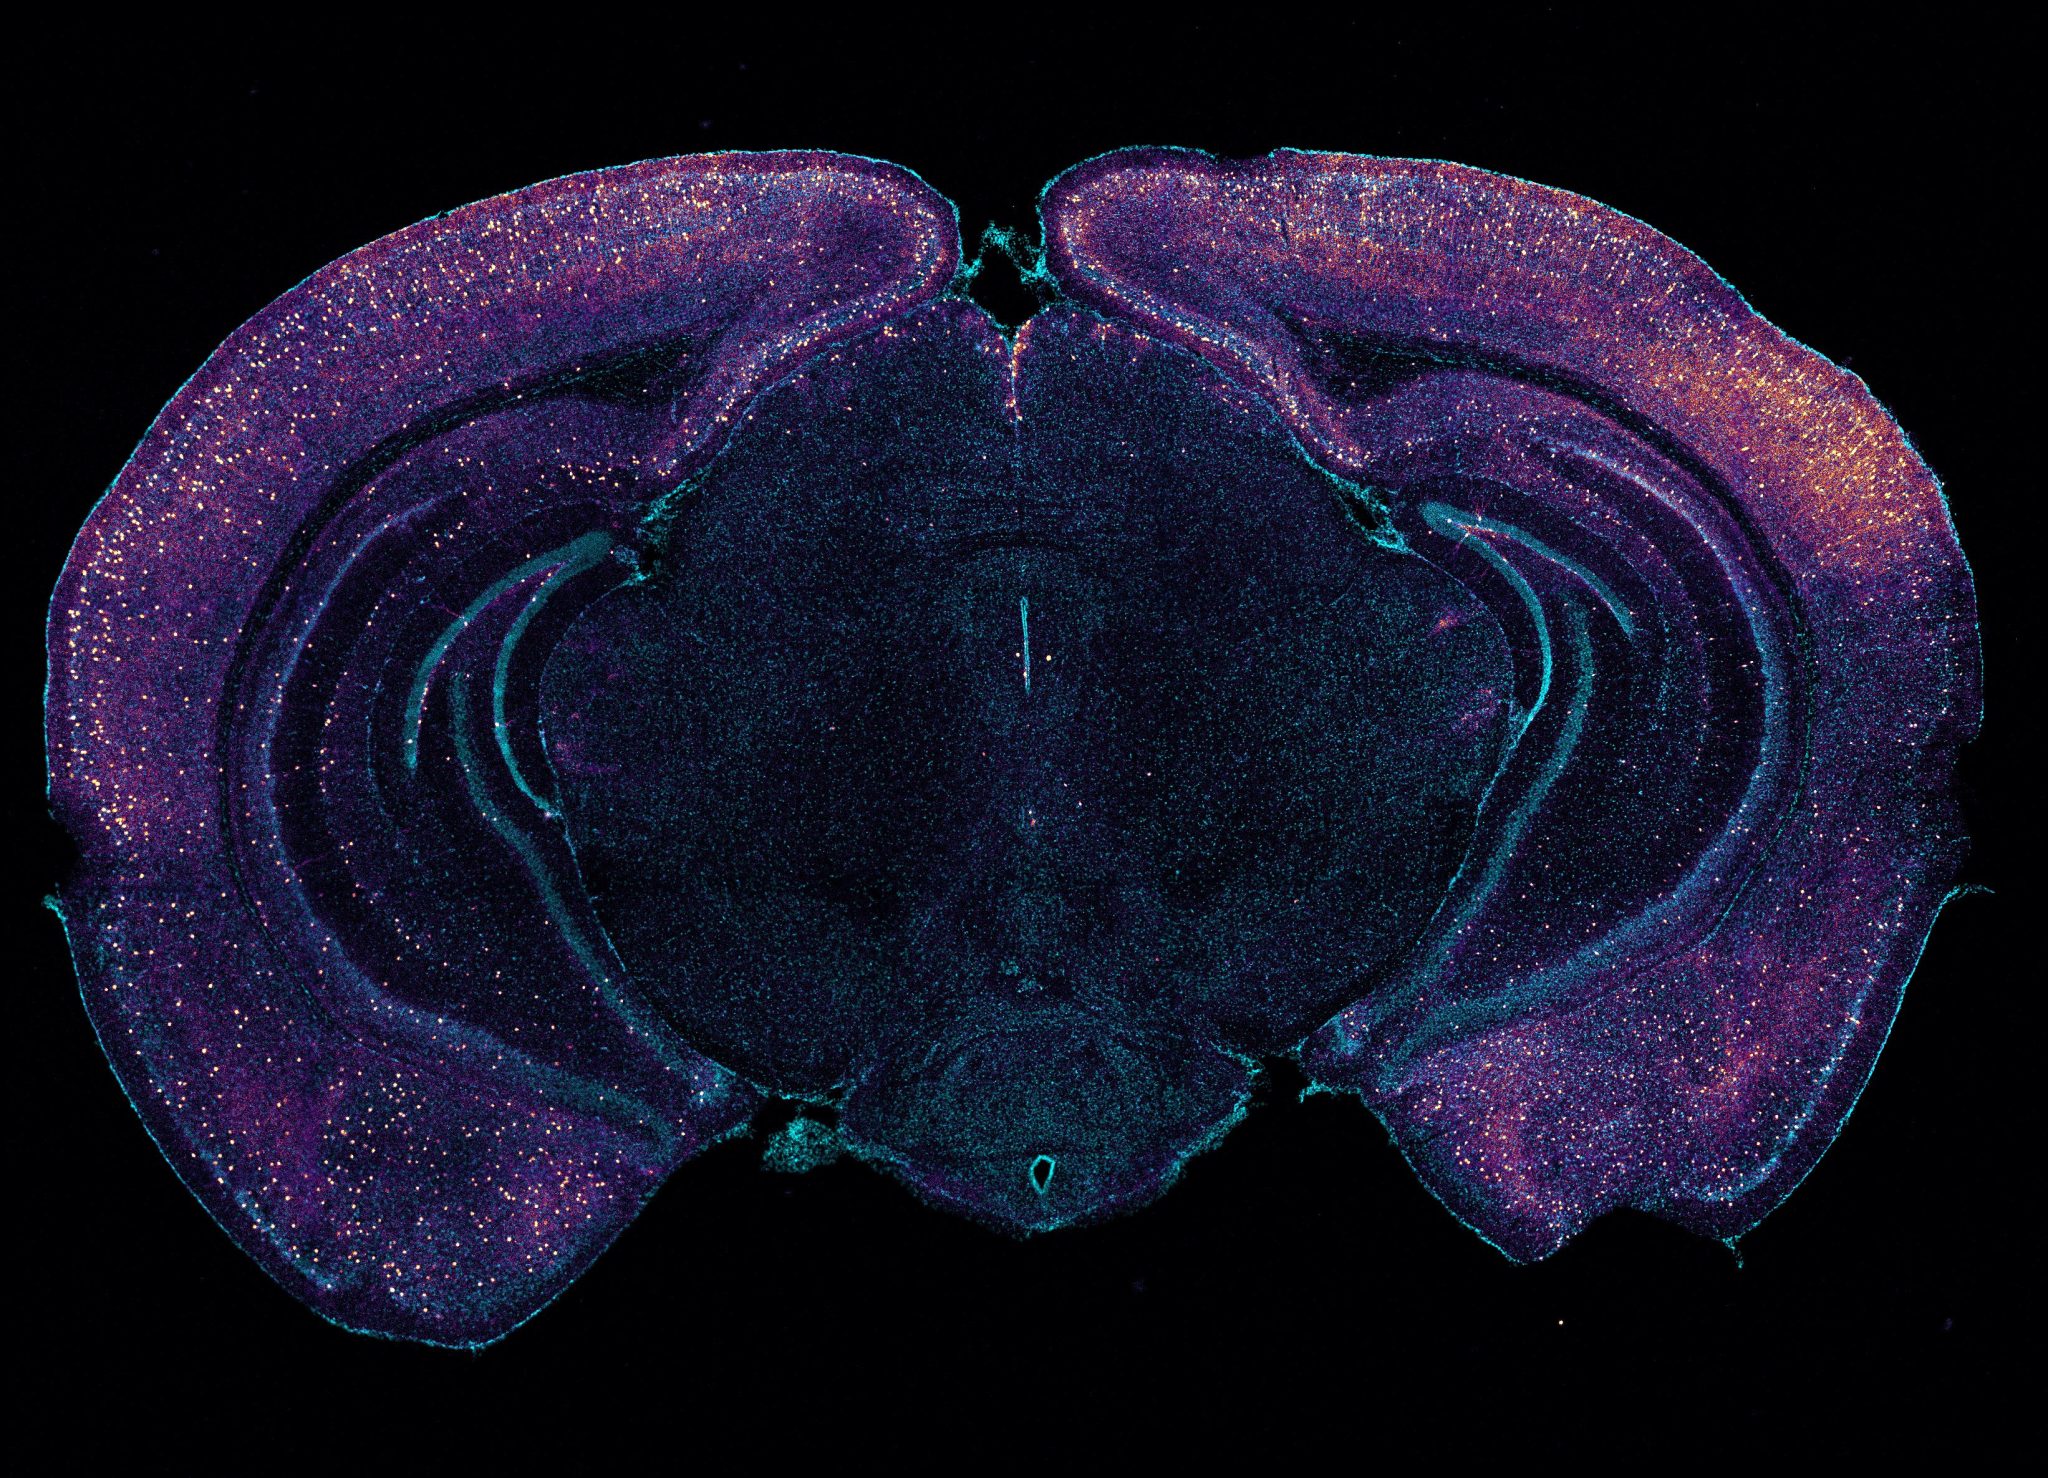

Evidence that noninvasive sensory stimulation of 40 hz gamma frequency brain rhythms can reduce alzheimer’s disease pathology and symptoms, already shown with light and sound by multiple research groups in mice and humans, now extends to tactile stimulation. Studies at mit and elsewhere are producing mounting evidence that light flickering and sound clicking at the gamma brain rhythm. Mit researchers have found that 40hz sensory gamma rhythm stimulation can significantly slow alzheimer's progression by enhancing the brain's glymphatic system to clear amyloid proteins. Audio and visual stimulation at 40 hz promote cerebrospinal and interstitial fluid flux in mouse brain and result in amyloid clearance.

Alzheimer S 40Hz Light Audio and visual stimulation at 40 hz promote cerebrospinal and interstitial fluid flux in mouse brain and result in amyloid clearance. Mit researchers have found that 40hz sensory gamma rhythm stimulation can significantly slow alzheimer's progression by enhancing the brain's glymphatic system to clear amyloid proteins. Audio and visual stimulation at 40 hz promote cerebrospinal and interstitial fluid flux in mouse brain and result in amyloid clearance. Evidence that noninvasive sensory stimulation of 40 hz gamma frequency brain rhythms can reduce alzheimer’s disease pathology and symptoms, already shown with light and sound by multiple research groups in mice and humans, now extends to tactile stimulation. Studies at mit and elsewhere are producing mounting evidence that light flickering and sound clicking at the gamma brain rhythm.